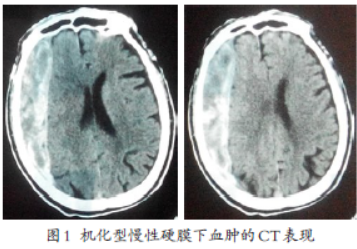

机化型慢性硬膜下血肿1例

病史摘要:91岁男性,主诉间断性头痛、头晕半年余,加重伴左侧肢体活动障碍1周。有头部外伤史年余,当时无症状。无癫痫发作。诊疗过程:入院查体神志清楚,精神稍差,言语对答尚流利,左侧肢体肌力Ⅲ级,病理反射阴性。头颅CT显示额颞叶骨板下新月形等密度高密度影占位,内有不规则高密度影分隔,周围有包膜样高密度信号,右侧脑室受压变窄,中线向左移位。采用气管插管全麻,行右额颞顶部骨瓣开颅血肿清除包

慢性硬膜下血肿